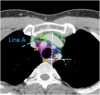

The purpose of this study was to develop a consensus-based computed tomographic (CT) atlas that defines lymph node stations in radiotherapy for lung cancer based on the lymph node map of the International Association for the Study of Lung Cancer (IASLC). A project group in the Japanese Radiation Oncology Study Group (JROSG) initially prepared a draft of the atlas in which lymph node Stations 1-11 were illustrated on axial CT images. Subsequently, a joint committee of the Japan Lung Cancer Society (JLCS) and the Japanese Society for Radiation Oncology (JASTRO) was formulated to revise this draft. The committee consisted of four radiation oncologists, four thoracic surgeons and three thoracic radiologists. The draft prepared by the JROSG project group was intensively reviewed and discussed at four meetings of the committee over several months. Finally, we proposed definitions for the regional lymph node stations and the consensus-based CT atlas. This atlas was approved by the Board of Directors of JLCS and JASTRO. This resulted in the first official CT atlas for defining regional lymph node stations in radiotherapy for lung cancer authorized by the JLCS and JASTRO. In conclusion, the JLCS-JASTRO consensus-based CT atlas, which conforms to the IASLC lymph node map, was established.